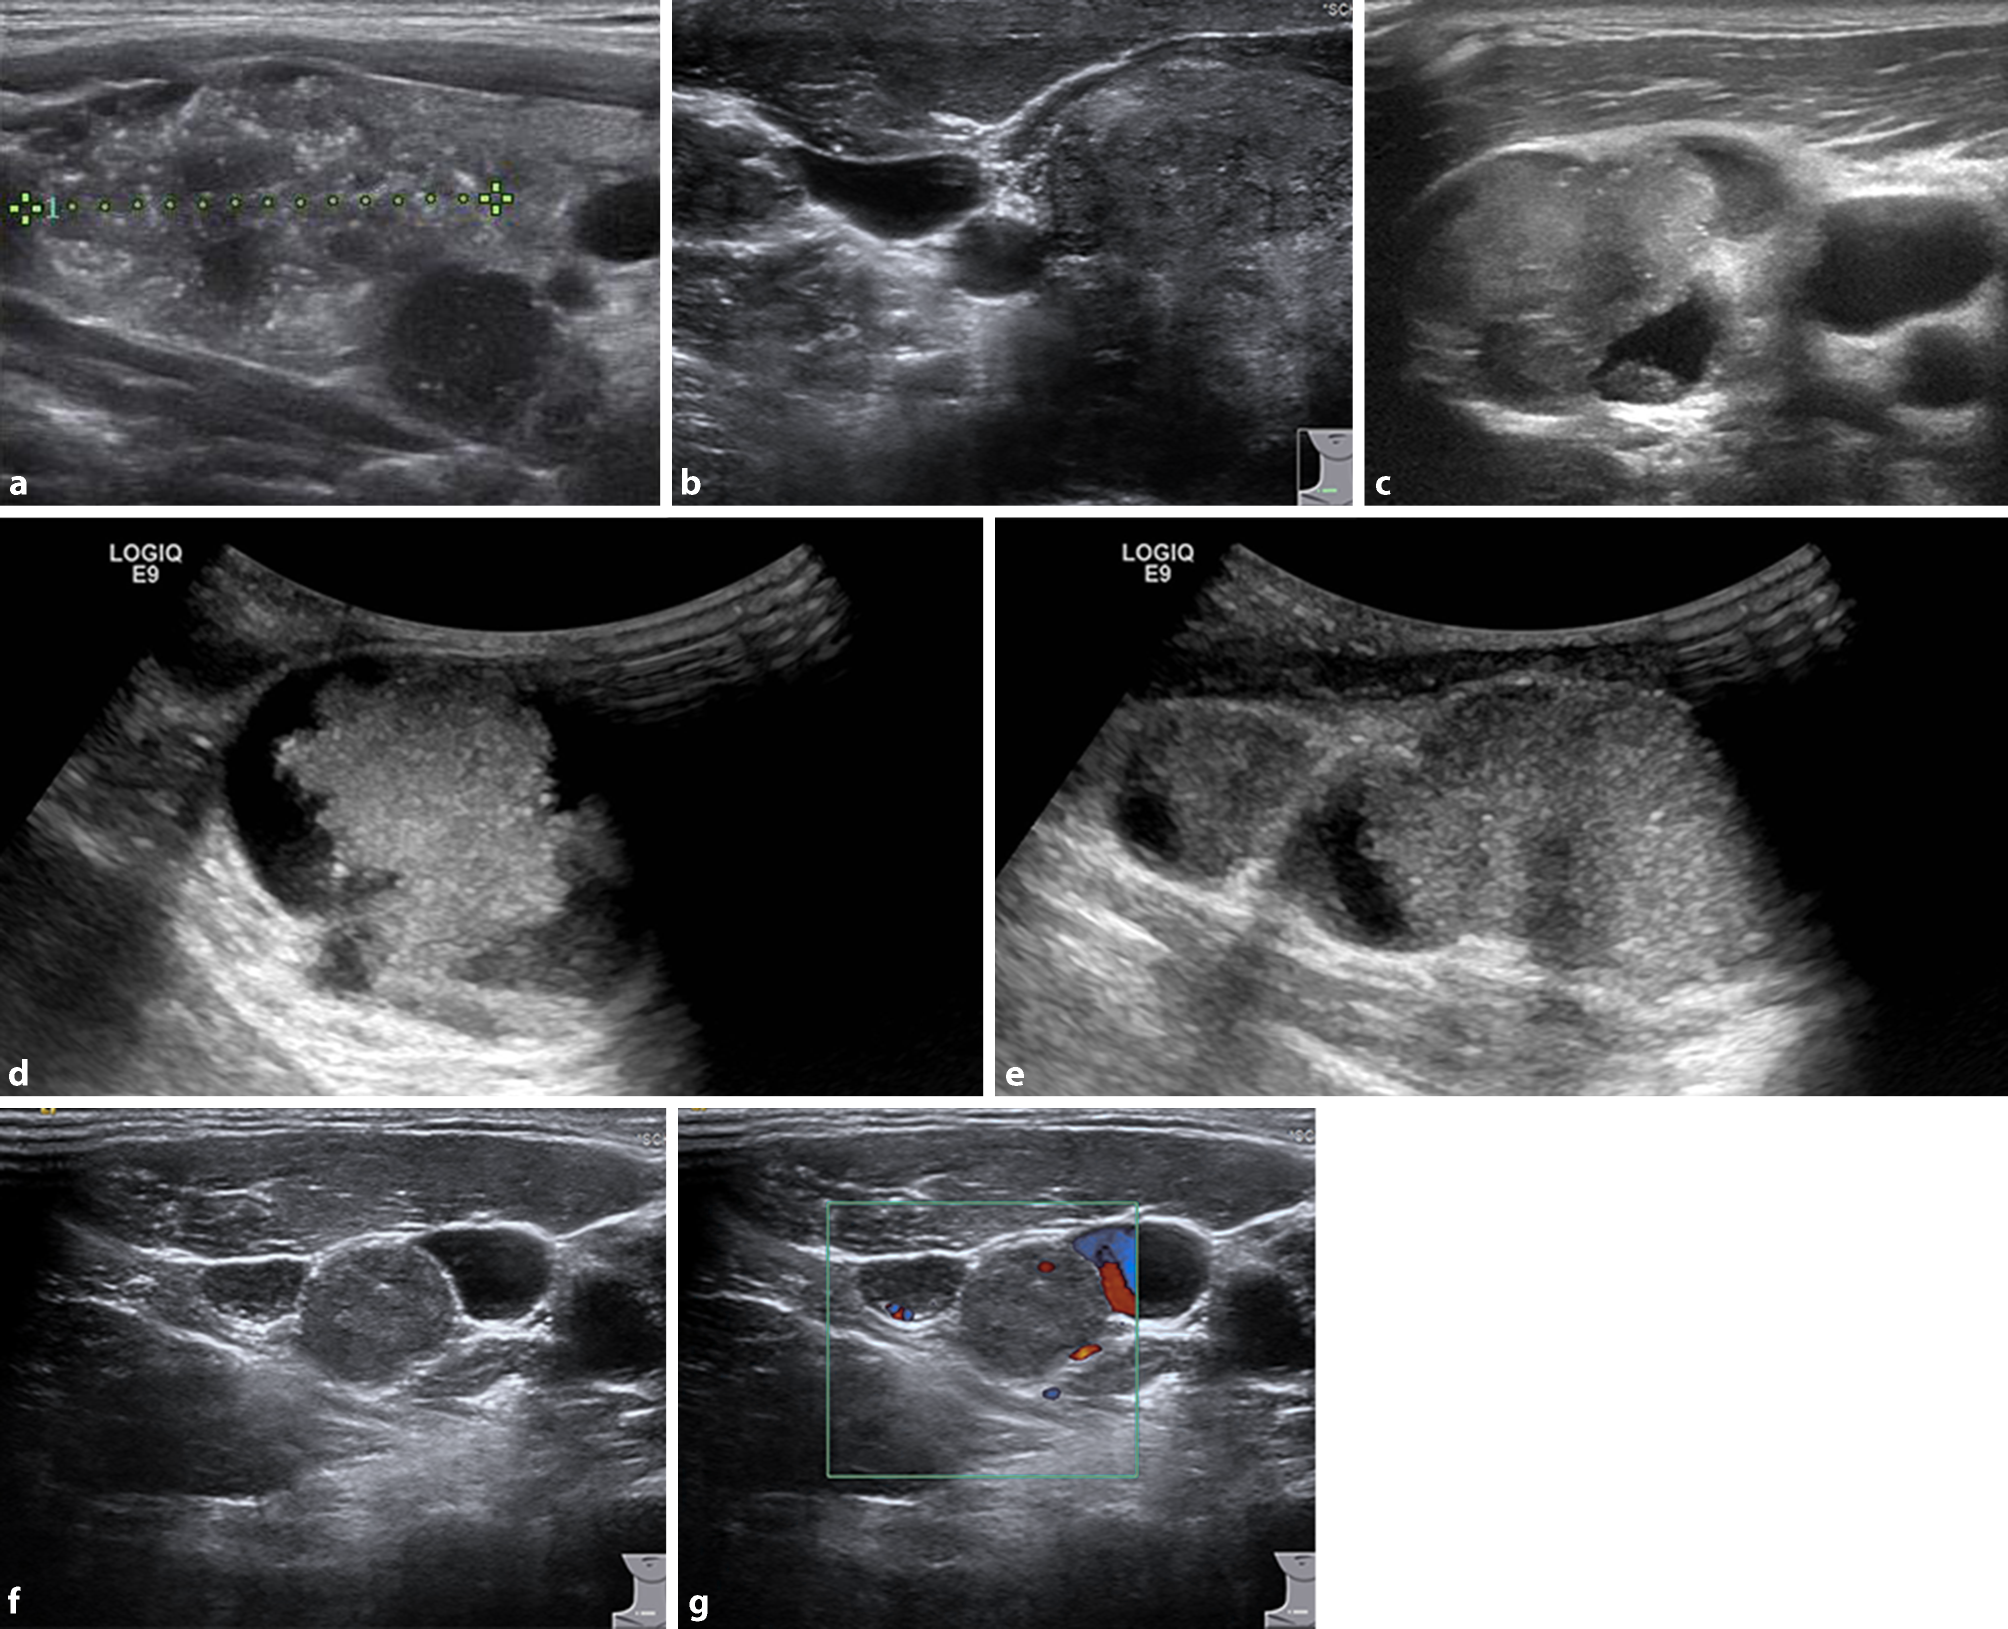

Abb. 1

a Typisches Muster eines papillären Schilddrüsenkarzinoms mit Mikrokalk – eine sonographische Blickdiagnose. b Querschnitt: rechts im Bild der Primärtumor eines papillären Schilddrüsenkarzinoms, in der Mitte Carotis und Jugularis, links eine Lymphknotenmetastase. ce Typische Sonographie von Lymphknotenmetastasen eines papillären Karzinoms mit soliden und zystischen Anteilen und Mikroverkalkungen. fg Parajuguläre Lymphknotenmetastase (Level IV)

Ist nicht mit letzter Sicherheit ein beobachtendes Vorgehen angebracht oder ein konservatives Behandlungskonzept zielführend und steht eine Operationsindikation im Raum, so sollte bereits zu diesem Zeitpunkt der endokrin versierte Chirurg zugezogen werden. Es wäre jedem Schilddrüsenchirurgen zu empfehlen, auch selbst eine Sonographie der Schilddrüse und der Halslymphknoten durchzuführen. Papilläre Schilddrüsenkarzinome (Abb. 1a,b) und deren solide oder auch zystische Lymphknotenmetastasen (Abb. 1c–g) können typische Muster aufweisen und auf einen Blick zu erkennen sein. So kann der Chirurg beurteilen, welches Radikalitätsausmaß bzw. Operationsverfahren im individuellen Fall sinnvoll und notwendig ist. Auch die Labordiagnostik muss entsprechend berücksichtigt werden und in das operative Konzept miteinfließen, beispielsweise erhöhte Calcitoninwerte und Interpretation von Calciumstimulationstests oder Evaluierung von erhöhten Parathormonwerten zur Differenzierung eines primären oder eines sekundären Vitamin-D-mangelbedingten Hyperparathyreoidismus. Jedenfalls ist zur Planung der Operationsstrategie die Kenntnis der Schilddrüsenfunktion, der Schilddrüsenantikörper, des Calcitonins und der Nebenschilddrüsenparameter – Calcium, Parathormon und Vitamin D – von essentieller Bedeutung (Tab. 1). Damit verbunden ist auch die Verantwortung des modernen Schilddrüsenchirurgen, nicht nur mechanistisch das Handwerk der Thyreoidektomie möglichst gut und komplikationsfrei zu beherrschen, sondern ein umfassendes endokrin-chirurgisches Verständnis in seine operative Strategie einfließen zu lassen.